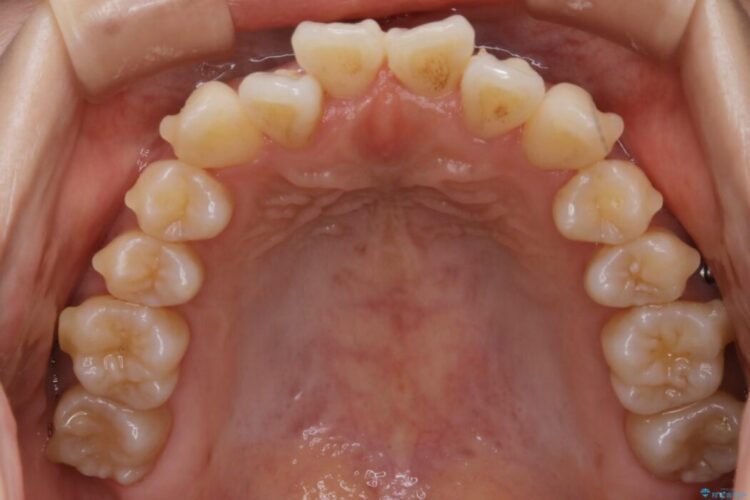

前歯のガタガタを気にされて来院されました。

検査の結果、骨の厚みに余裕がないことが判明しましたので、幅の拡大と歯の側面を削るIPRでは歯周病に対する不安を拭いきれないと判断しました。

よってマイクロインプラントを用い、奥歯から順番に遠心移動させることによってスペースを確保することにしました。